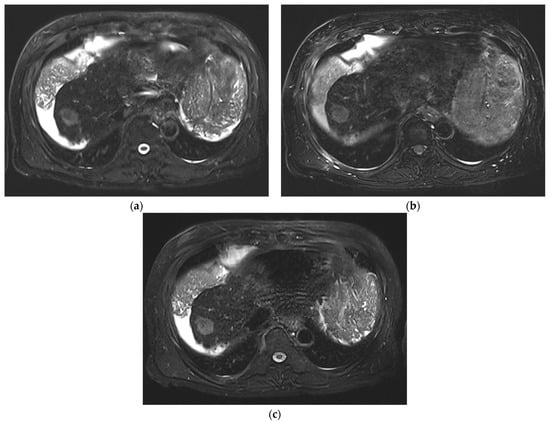

3. Results

3.1. Subjective Image Quality

3.2. Lesion Assessment